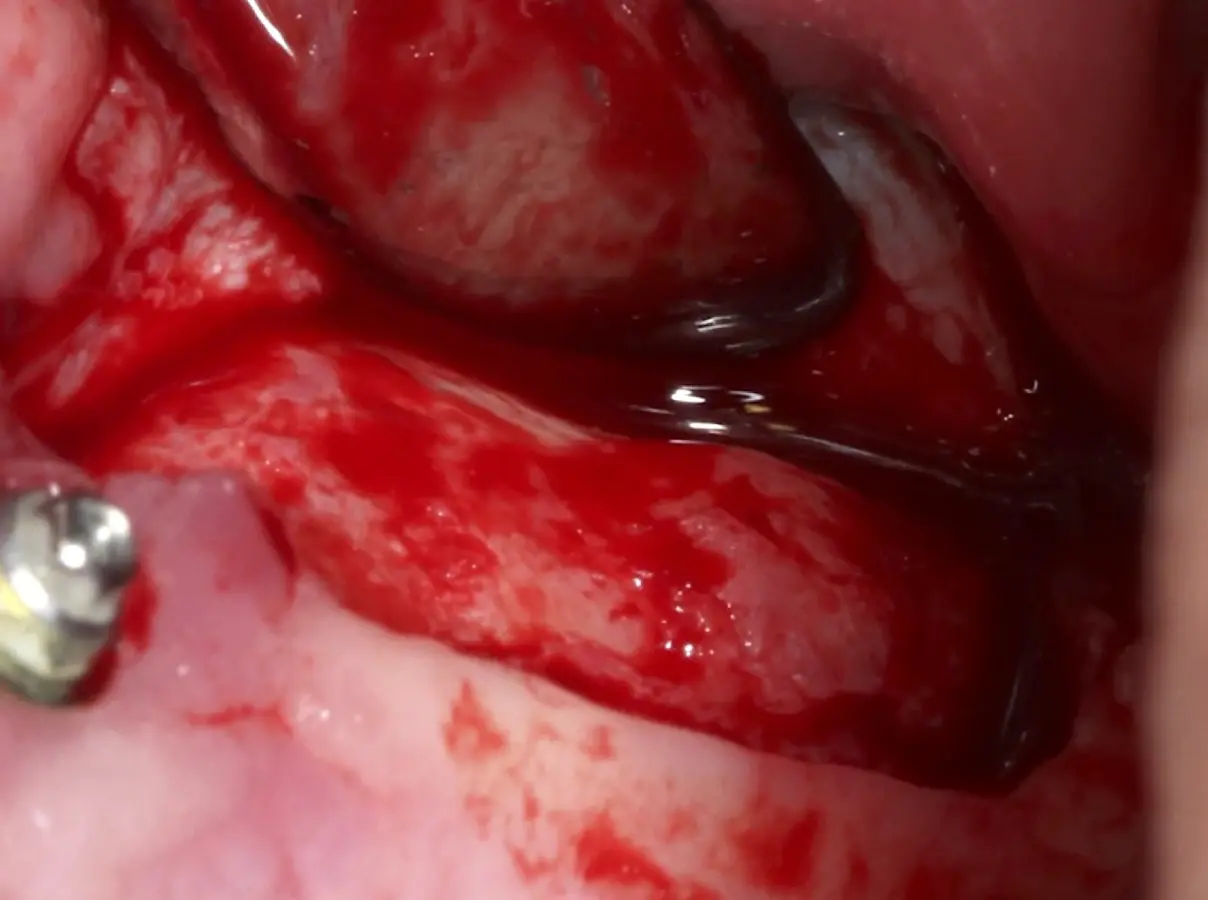

Figura 18. Elevación de la membrana de Schneider con curetas manuales (a, b).

Figura 19. Colocación de membrana de PRF dentro del seno maxilar como protección de la membrana de Schneider.

Figura 26. Decolado de la membrana de Schneider hasta la pared medial del seno maxilar (a). Desplazamiento de la pared ósea lateral al interior del seno maxilar transformándose en parte del techo de la ventana o nuevo piso del seno (b).